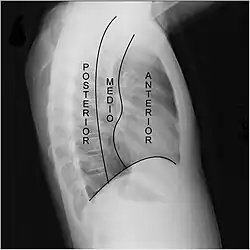

Radiografía lateral de tórax en la que pueden observarse los tres compartimientos del mediastino (Felson).

Una segunda clasificación divide el mediastino desde el punto de vista radiológico en tres zonas: anterior, media y posterior. Esta división propuesta por Felson utiliza como referencia la radiografía lateral de tórax. El mediastino anterior y medio quedan separados por una línea imaginaria que se extiende desde el borde posterior de la silueta del corazón al borde anterior de la tráquea. El mediastino posterior y medio se encuentran separados por una línea situada un centímetro por detrás del margen anterior de los cuerpos vertebrales.[8][9][10]